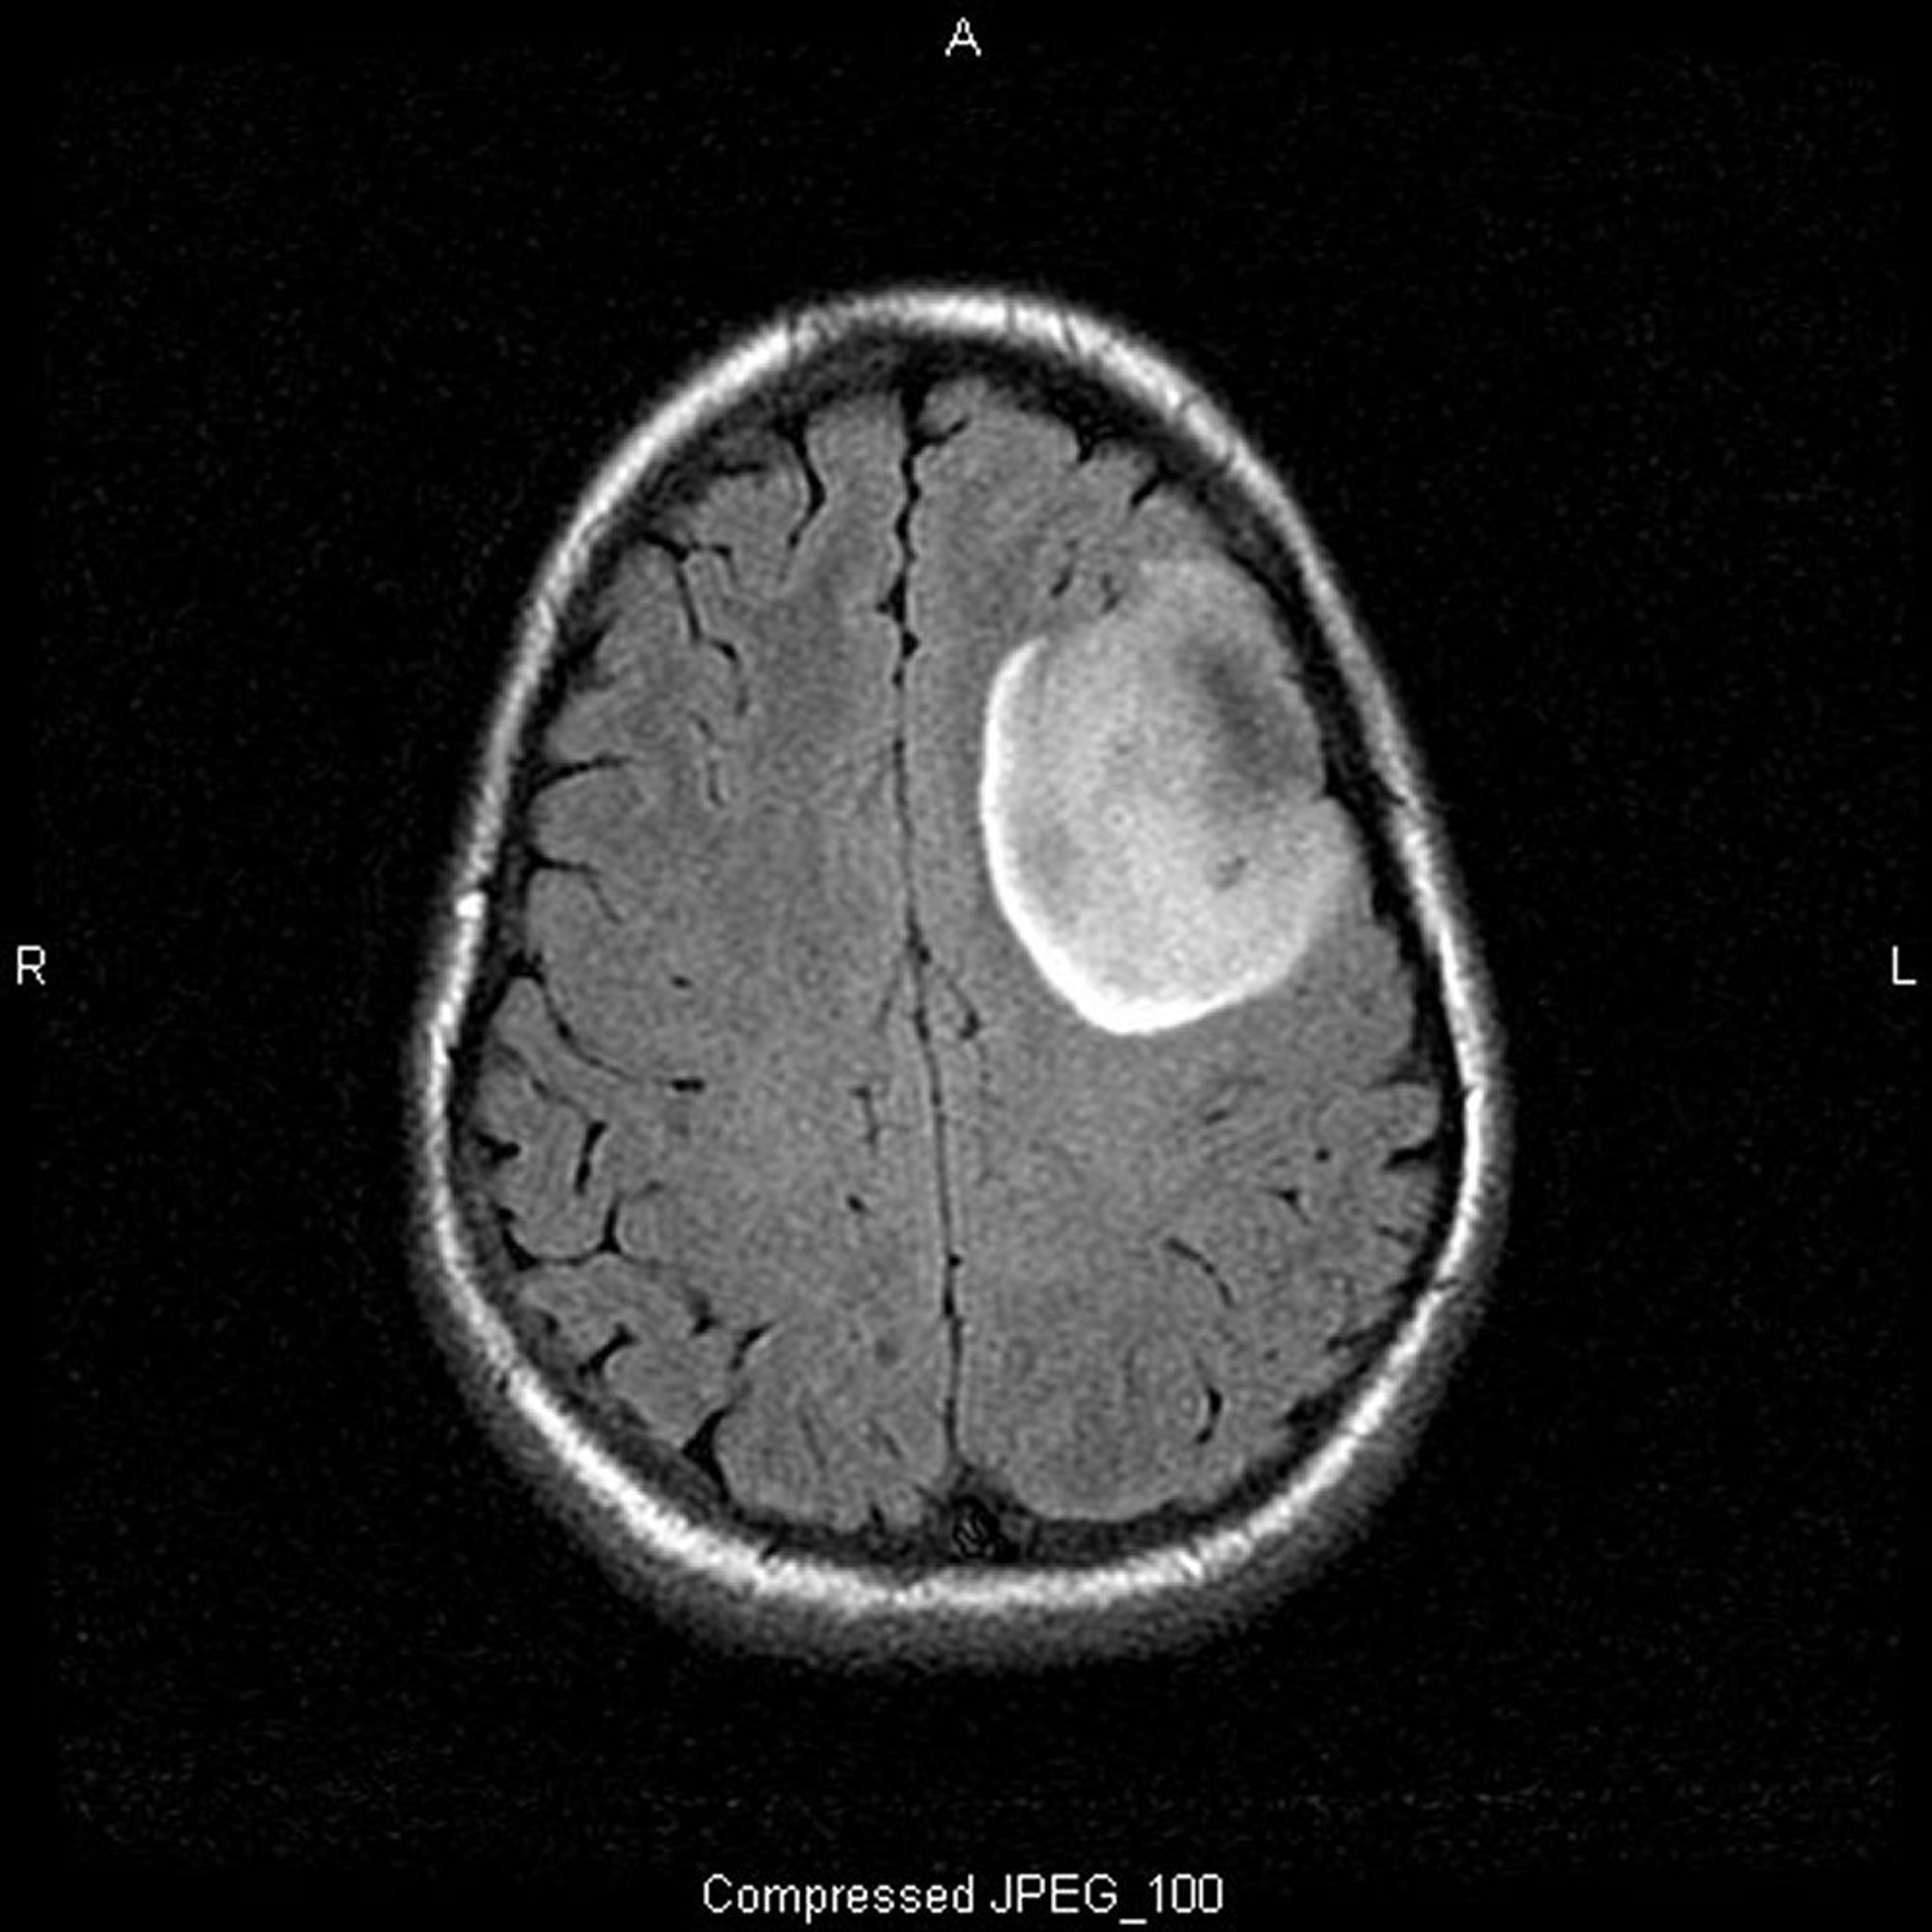

Oligodendrogliome de bas grade

Cette IRM T2-FLAIR (fluid-attenuating inversion recovery) montre un signal blanc, qui peut indiquer une masse ou un œdème. Le signal frontal gauche est très délimité, suggérant une masse. L'utilisation d'un produit de contraste ne le rehausse pas. C'est un oligodendrogliome de bas grade (grade II).

Image courtoisie de William R. Shapiro, MD.